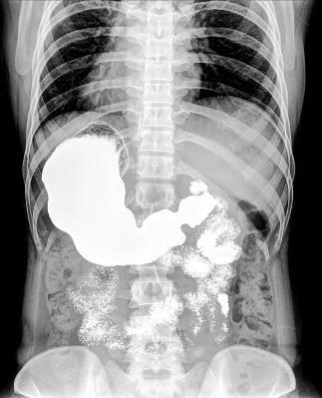

Иллюстрация к книге — Взламывая анатомию [image200.jpg]

Желудочно-кишечный тракт можно рассмотреть при исследовании с помощью бариевой взвеси. Этот особый тип рентгеновского исследования помогает врачам наглядно изучить верхние отделы ЖКТ.